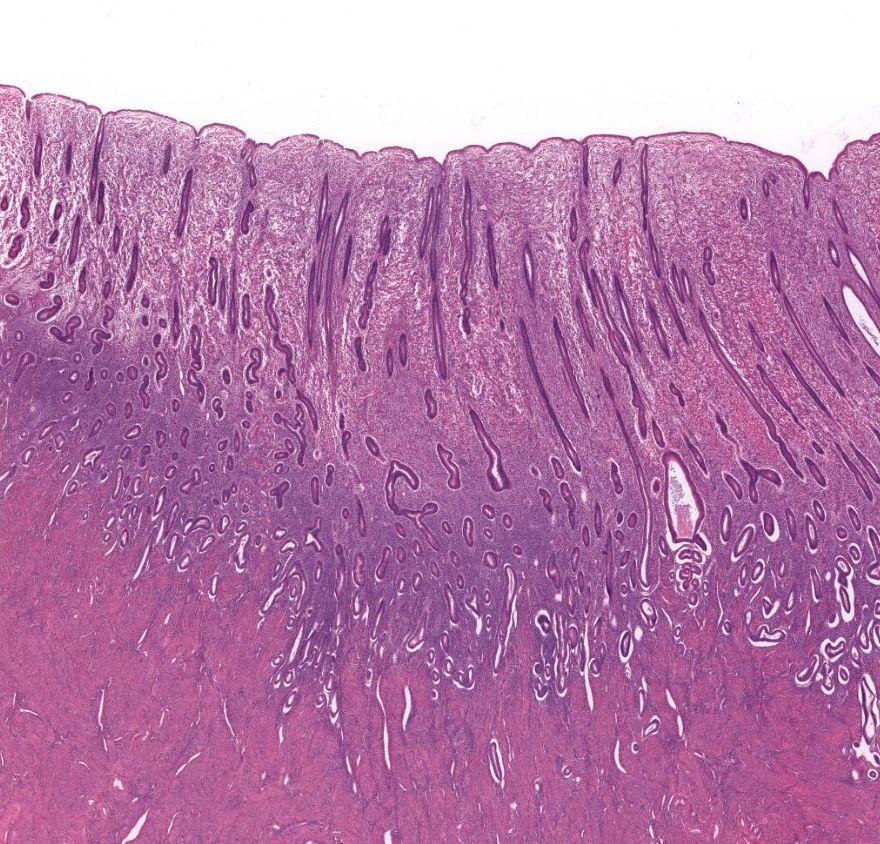

Fundo do estômago